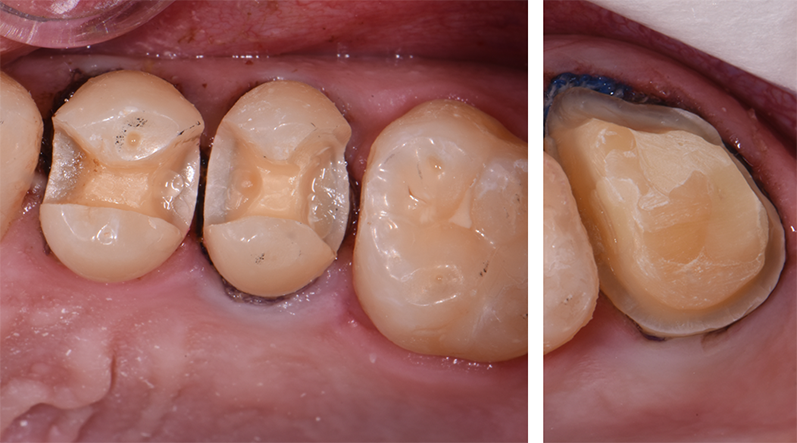

Inlays and crown were prepped, and the rubber dam was removed for photos (Figs. 8-9).

Fig. 8 Fig. 9